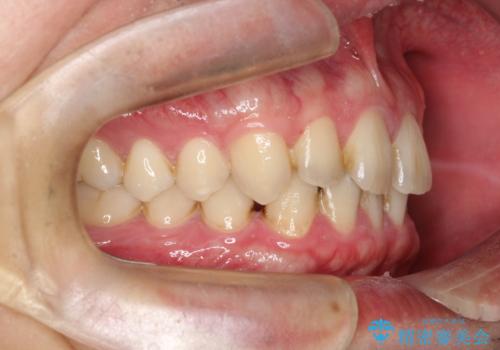

【インビザライン】前歯の隙間を治したい。

- 前歯の隙間を主訴に来院されました。

インビザラインにて治療しました。

ディープバイトも改善でき患者さんも満足されていました。

前歯の隙間だけを閉じる治療を行うだけでは、噛み合わせが悪くなるためディープバイトも改善が必要です。